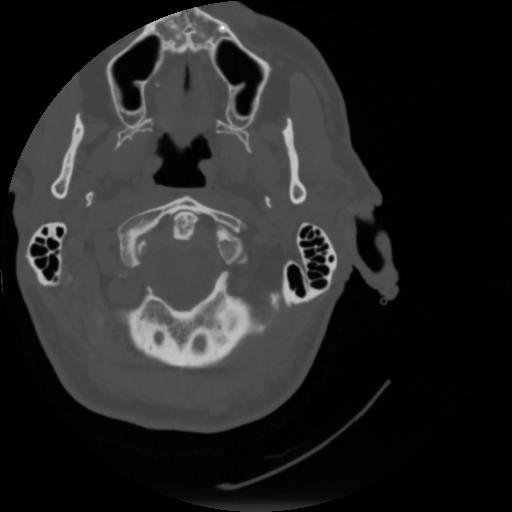

4 CEREBRO,,Vol,0.5,CEREBRO,,